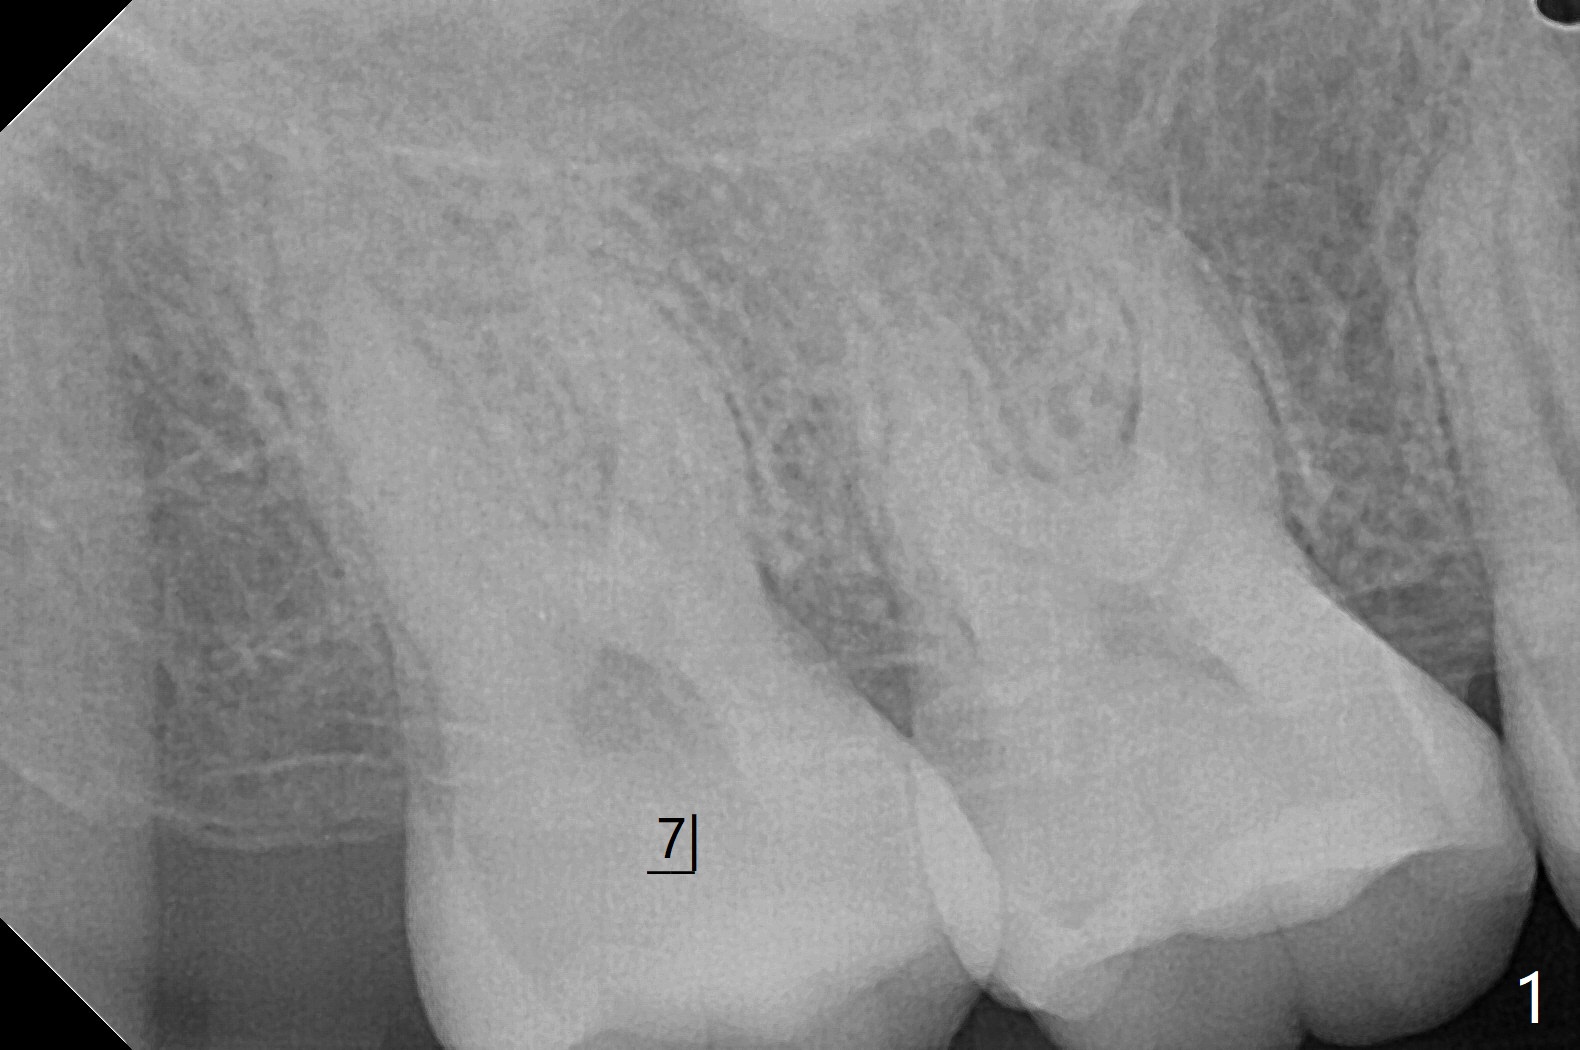

31岁女去年10月份就诊,右上7隐裂(图一),提出根管治疗,牙冠或者拔除,植牙。她犹豫不决,因为今年6月份回国。昨天因腭侧脓肿深度牙周袋复诊,最后同意拔除,植骨。使用GEM21S(血小板因子,没有时间抽血)与皮质骨粉(加一些人工骨)调袢(图二:*),覆盖不可吸收膜(Cytoplast,一张~$50,剪半可用于两个磨牙牙槽窝,买一盒十张,赠送两个PTFE缝线(最近促销);图三)。PTFE,Cytoplast以及Plumber tape据说来自同一个材料,至少前两者最好同时用。但是这个病例,助手打开PGA缝线后,我们才知道Cytoplast刚刚到,它的好处在于暴露于口腔,下面骨粉几乎不会感染。五周后撤除 ,下面骨粉一般愈合正常,接近百发百中。想不到垂直距离特别短,没有空间放置空间保持器,后者有利于牙周敷料固定,下颌第二磨牙牙尖咬到保持器攀(loop),尽管保持器已经放置第一磨牙颈部。无可奈何,在缝线周围涂牙周胶水(图三:蓝紫色)。术后两周膜已经脱落(图四),但是下面骨粉好像没有丢失太多(图五)。两周后伤口愈合(图六)。骨粉失去不多(图七)。